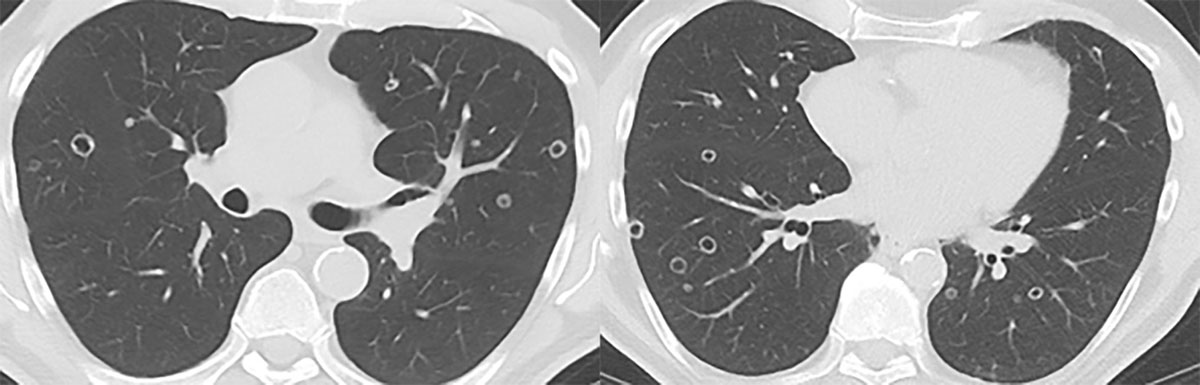

In November 2020, PSA-levels increased to 6 ng/mL and a third follow-up F18-PSMA-PET-CT revealed multiple, thin- and thick-walled, excavated, pericentrimetric, randomly distributed, nodular lung lesions with a slightly metabolic avid wall bilaterally (Figure 1) and enlarged para-iliac lymph nodes. The lymph nodes were treated with three sessions of stereotactic body radiation therapy in January 2021. The lung nodules were not treated, as their metastatic potential was considered low based on their morphology. A fourth F18-PSMA-PET-CT in May 2021 (Figure 2) and a CT-thorax in June 2021 (Figure 3) showed PSMA-uptake and increased volume and number of the cavitary lung nodules. A broad differential diagnosis of vasculitis, granulomatous disease, infectious/septic embolisms and atypical metastases was suggested.

Figure 3